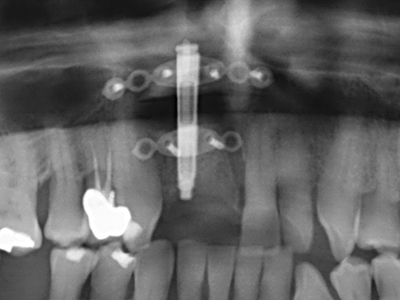

Fig. 21: Extended maxillary anterior-tooth defect with indication for distraction osteogenesis with scar tissue after prior operation.

Fig. 22: The mobile segment can be precisely separated with the thin osteotomy saw (W&H Piezomed).

Fig. 23: Final mobilization of the palatally branched distraction segment with the chisel.

Fig. 24: Application of the distractor (TRACK-System, KLS Martin).

Fig. 25: Panoramic image after reaching the final distraction height, before consolidation period.

Fig. 26: Stable conditions before implant placement after a consolidation period of four months.